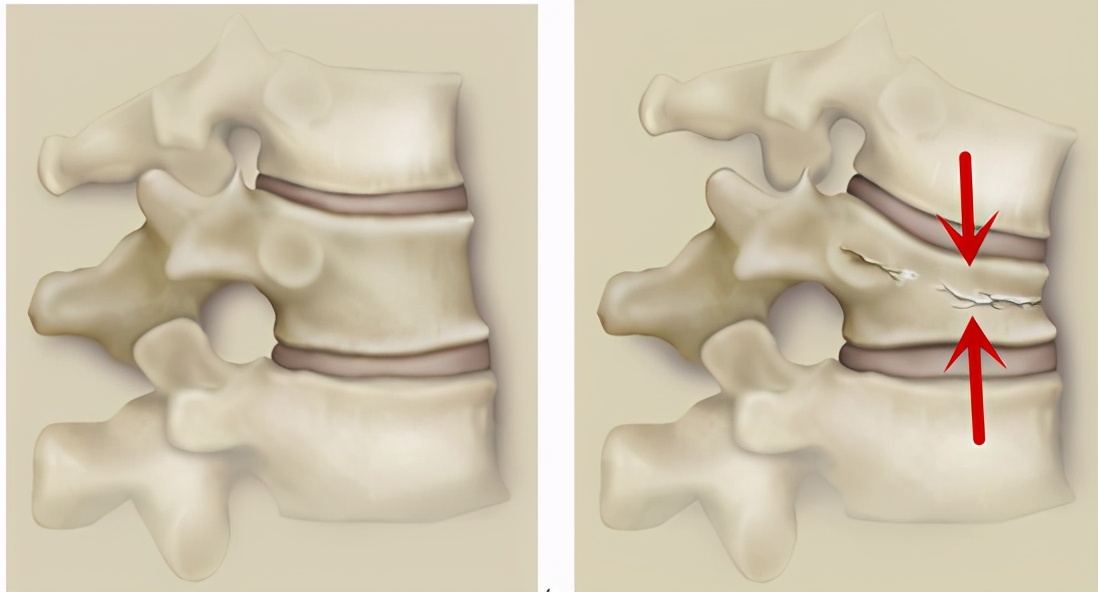

这种骨折是压缩性骨折,如下图,左边所示是正常椎体,而右侧红色箭头就是椎体呈压缩状态。

此骨折比较稳定,虽然已经骨折,但是除了会压缩更厉害以外,骨折并不会出现较大范围的移位,因此一般不会出现瘫痪等严重的并发症。只是会在扭动身体的时候感觉到腰背部的疼痛,也就是通常所说的“翻身痛”,这种病人在站起来以后甚至可以走路。